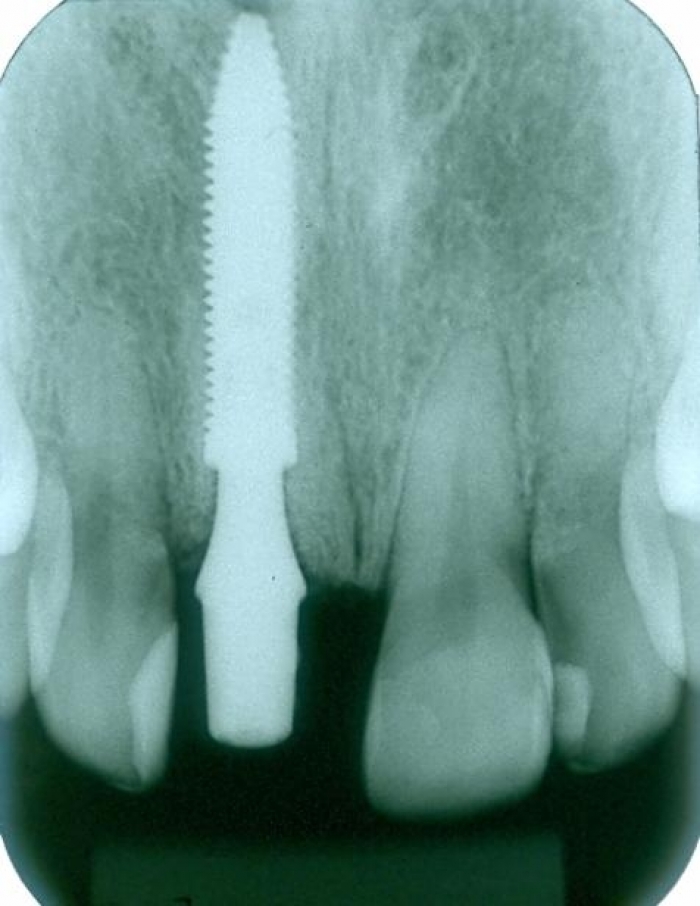

Raio X da prótese provisória

Prótese provisória fixa sobre implante cone Morse